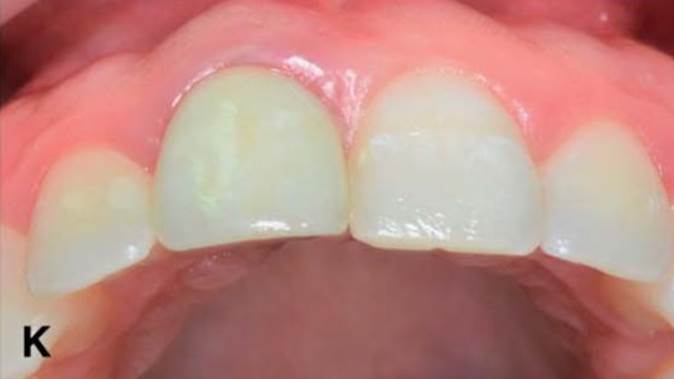

Clinical case: Replacement of fractured central incisor (#11) with immediate implant

& Root Membrane Technique

- Courtesy of Dr. Miltiadis Mitsias, Greece -

AnyRidge, Root Membrane Technique, retrospective study, long-term study, immediate implants, bone resorption, bone preservation, Dr. Miltiadis Mitsias,survival, success, maxillary anterior, single replacement

AnyRidge implant system, Root Membrane kit

The Root Membrane Technique: A retrospective clinical study with up to 10 years of follow-up./Implant Dent. 2018 Oct;27(5):564-574

https://www.ncbi.nlm.nih.gov/pubmed/30161062